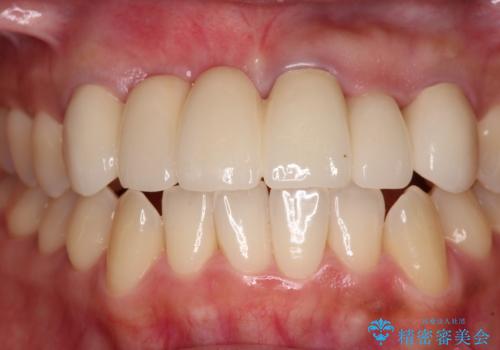

長く見える歯を治したい 歯肉移植による歯肉増大術

歯肉が痩せてしまっている状態を改善するため、口蓋から歯肉の結合組織を採取し、移植することで厚みを増大させることとし、その後オールセラミックブリッジにて補綴治療を行うこととしました。

1回の歯肉移植により歯肉の厚みは大幅に改善されましたが、折角なのでもう少し大きくしたいとの要望があり、2回目の処置も行うこととしました。

厚みも高さも十分な歯肉量を獲得することができました。